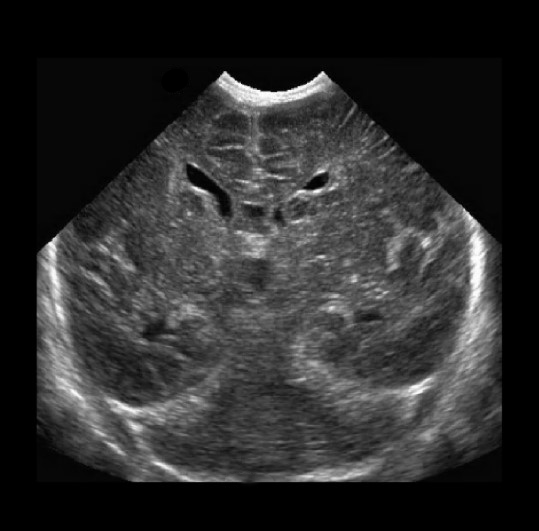

Neonatology Germinolytic Cyst 2 Image